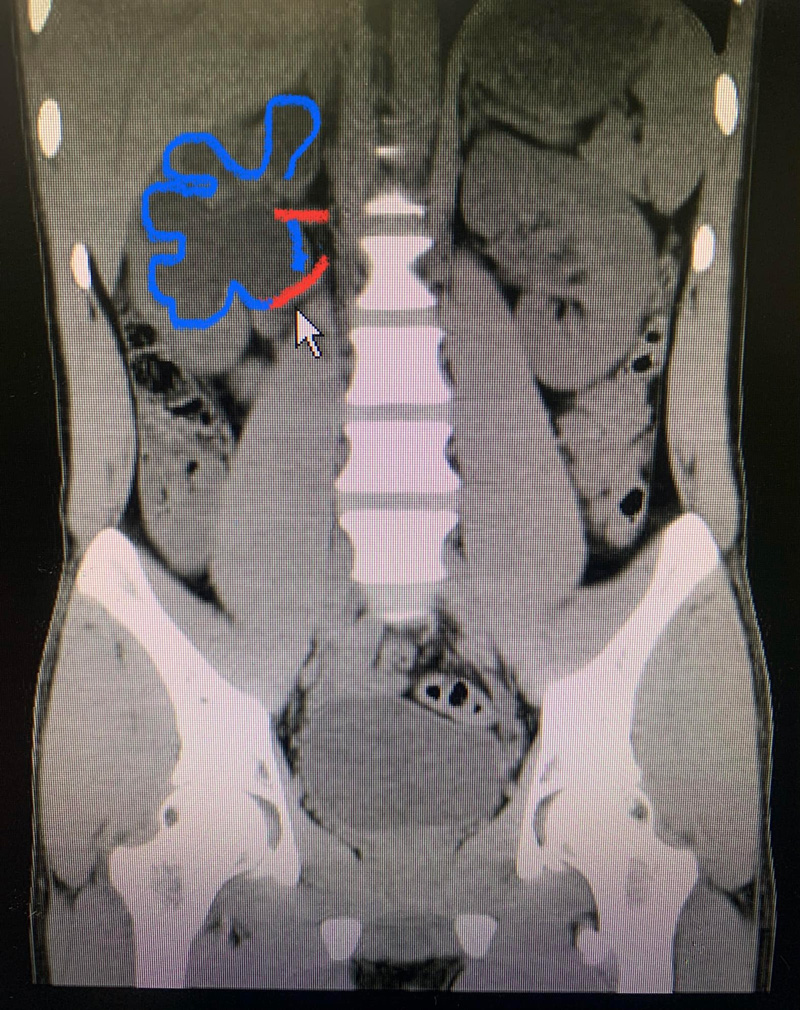

โดยที่คุณหมอบอกว่า คนไข้รายนี้ปวดหลังด้านขวามา 5 ปี และไปตรวจกับหมอกระดูกไม่เจอ เมื่อทำอัลตราซาวด์และเอกซเรย์คอมพิวเตอร์ ก็พบว่าไตขวาบวมเนื่องจากมีเส้นเลือดแดงเพิ่มมาอีกเส้น (เส้นสีแดงล่าง) และเส้นเลือดแดงนี้ไปกดทับท่อไต จนไตบวมน้ำ

ภาพจาก เฟซบุ๊ก Sirianan Prasit

ทั้งนี้ คนเราจะมีเส้นเลือดแดงที่ไตด้านละเส้น หรือบางคนมีเส้นเลือดไตเส้นที่ 2 เข้ามาด้วย และถ้าเส้นเลือดนี้ไปกดทับท่อไต ก็จะส่งผลให้มีอาการปวดหลังเรื้อรังได้ และในเคสนี้ต้องเข้ารับการผ่าตัดเพื่อต่อท่อไตใหม่